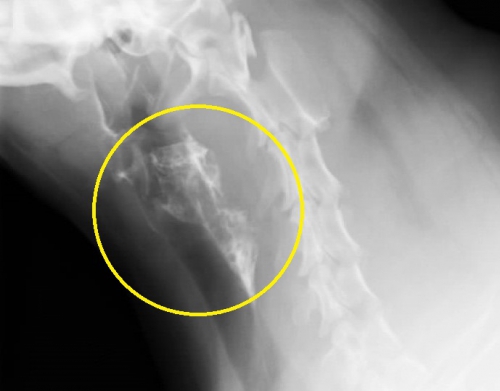

飼い主さんの訴えから、やはり上部消化管の異物、おそらく骨だろうと考えて胸部と腹部そして頚部のレントゲン写真を撮影いたしました。

頚部レントゲン写真には、わんちゃんの骨格と違う「骨のレントゲン像」が見えます。(下写真の黄色矢印)、レントゲン写真にて異物の確認ができましたので造影検査は行わず、当日に内視鏡により摘出いたしました。

このように骨のような硬い異物になるとレントゲンに写りやすくなってきます。